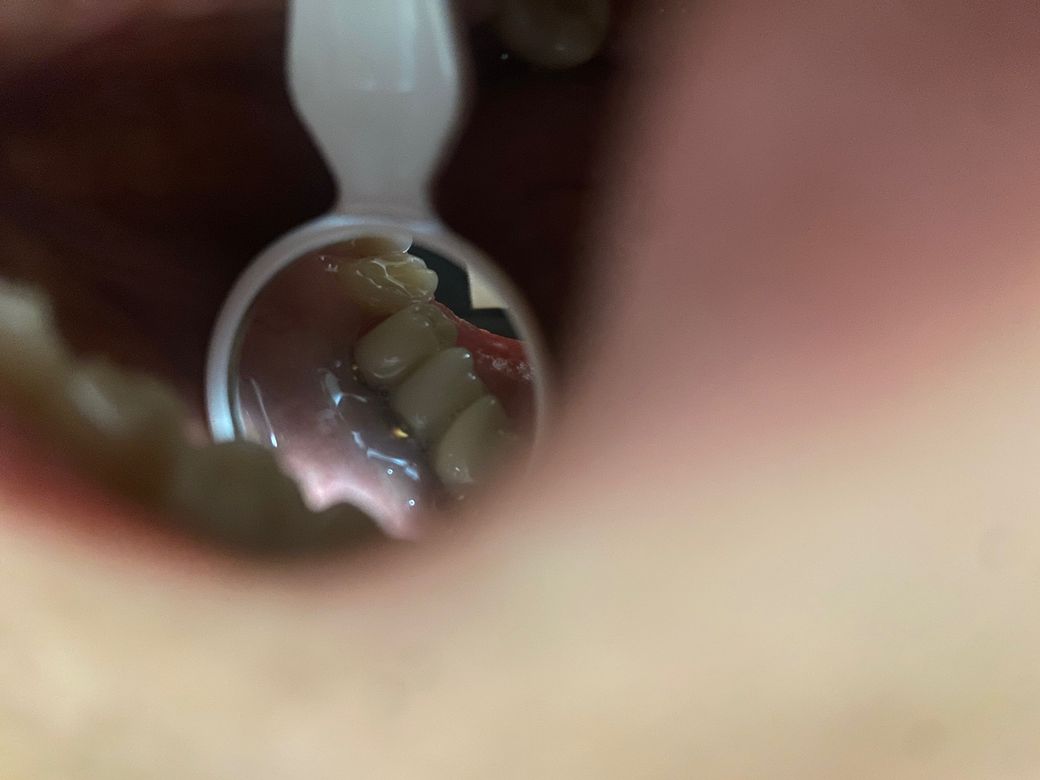

임플란트를 2016년에 식립한 후 현재까지 사용 중입니다. 거의 8년차가 되니 점점 잇몸이 내려 앉고 임플란트.지대주가 보이기 시작했습니다.(1~2mm)정도

• 1번 째 사진